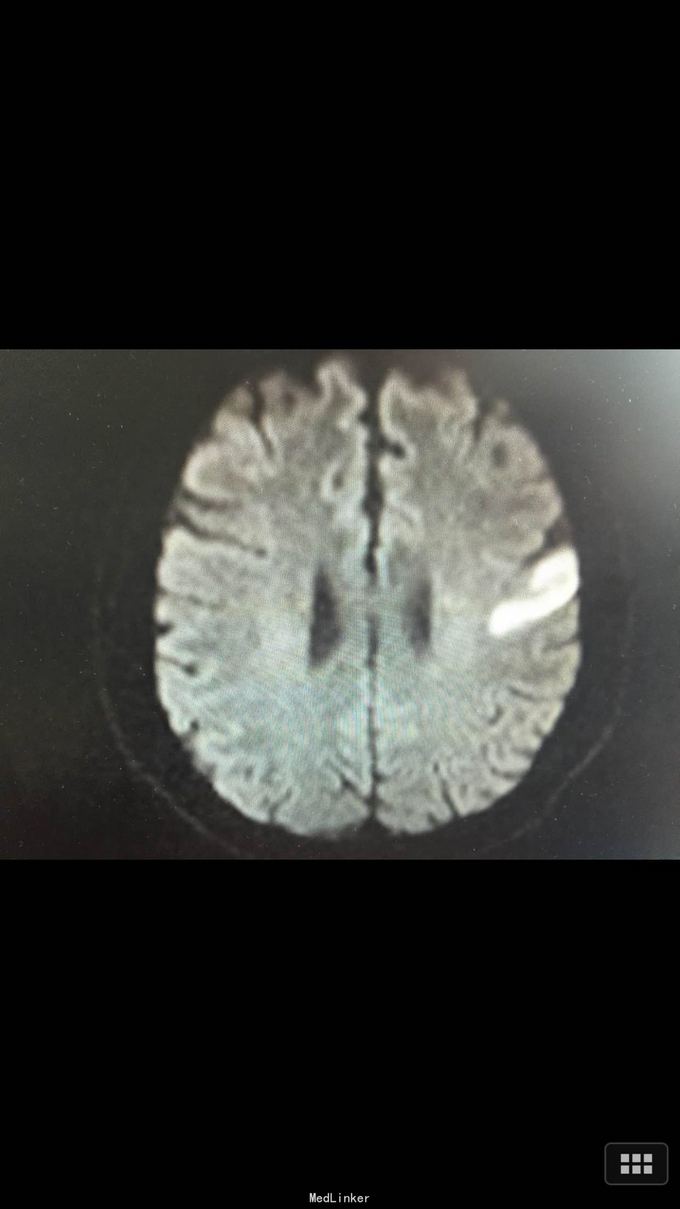

查体:BP:140/100mmHg,心肺腹无异常,神志清醒,完全运动性失语,右侧中枢性面瘫,四肢肌力、肌张力正常,腱反射正常,巴氏征R-L-,左足弓形足。 化验:血糖:14.3mmol/l,血脂:总胆固醇:13.29mm0l/l,LDL:6.6mmol/l,甘油三酯:24.51mmol/l。 影像学: